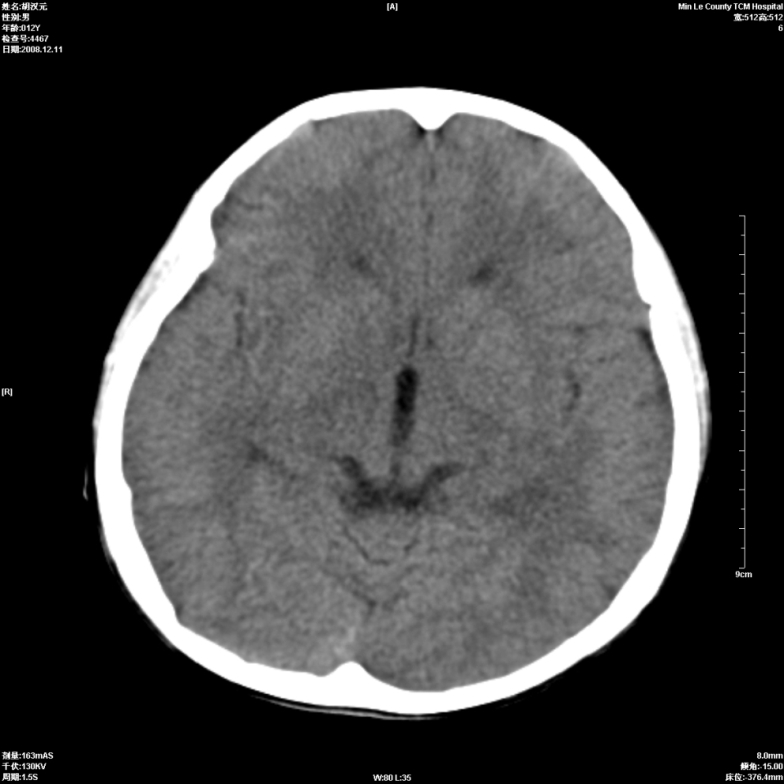

标题: PED1681:头疼发热约一周 [打印本页]

标题: PED1681:头疼发热约一周

颅脑未见确切异常。必要时进一步检查,如mri、脑脊液检查。

两侧顶部近灰质处白质密度降低,是否炎性改变

颅脑ct轴位平扫颅内未见明确异常;建议必要时复查或行进一步检查。

两侧顶部近灰质处白质密度降低,建议mri